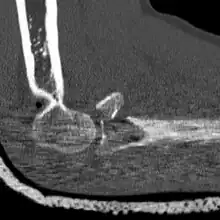

CT scan showing a radial head fracture